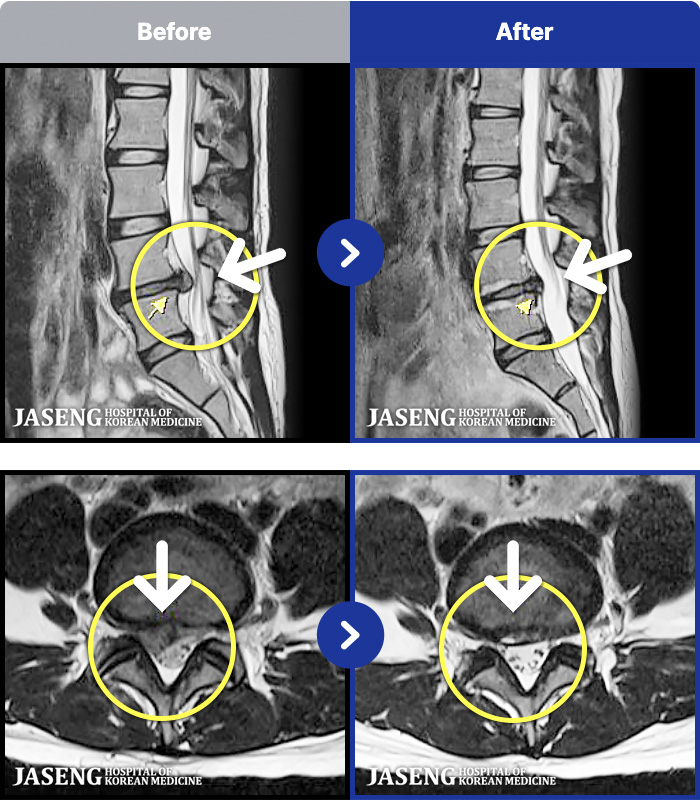

MRI ġ

MRI ũ ʸ Ȯϼ.